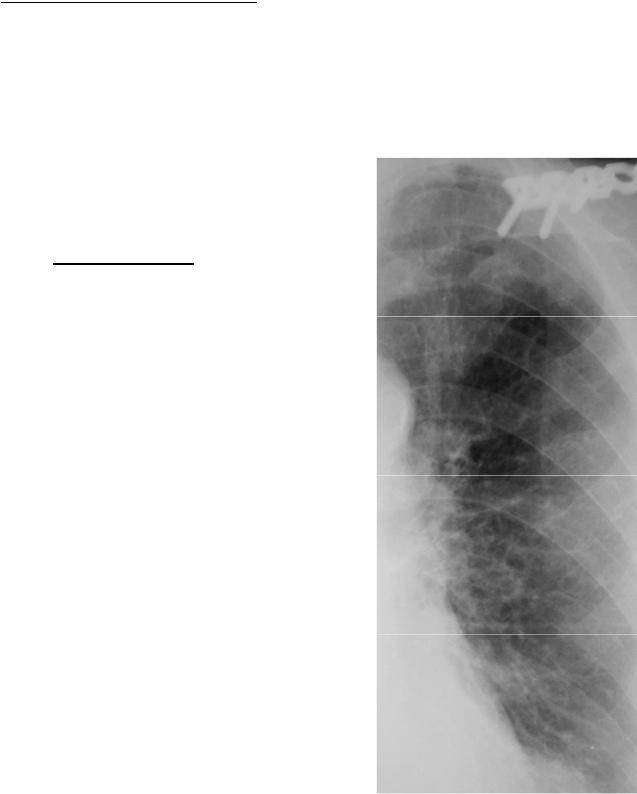

Изучение дозы излучения при рентгеновских исследованиях: визуализация